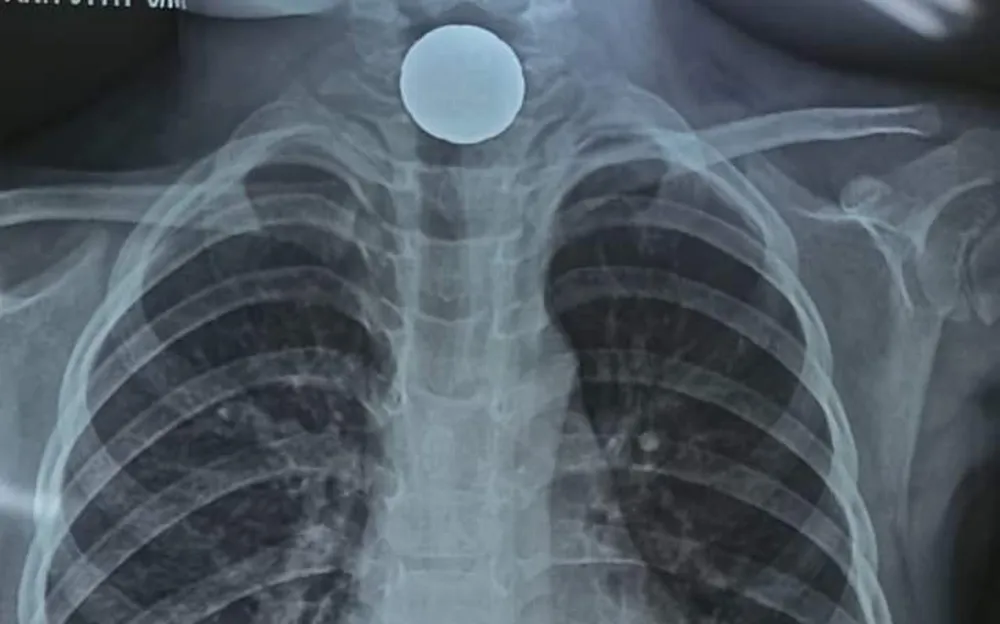

Sau khoảng 10 phút nội soi, dị vật là một đồng xu hình tròn, đường kính khoảng 2cm, màu vàng đã được lấy ra khỏi thực quản bệnh nhân A.

| Đồng xu sau khi được gắp ra ngoài |